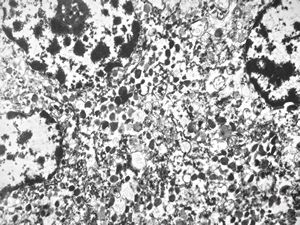

F, 36y. | chemodectoma - neck